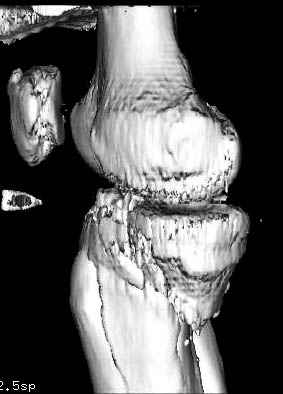

Пациенту сделали КТ - ухитрились сделать на шине Белера (не давал положить прямую ногу) - срезали передний отдел. Планируется на пятницу (24.12) на операцию - синтез длинной мыщелковой LCP-пластиной Synthes :). Отек ближе к слову умеренный (окружность голени +4 см по сравнению со здоровой). КТ и снимок на вытяжении прилагаются.

Здесь как раз тот случай, когда результат зависит не только от мастерства хирурга, но и от наличия современных методов исследования. Например, КТ которая поможет рассчитать направления шурупов и установку импланта. Кроме этого, поможет определиться с доступом.

На представленных предоперационных срезах КТ огромный задне-медиальный фрагмент расположен больше кзади, чем медиально. Для планирования, кроме поперечных срезов, надо ориентироваться на корональные срезы, которые укажут топографию верхушки медиального фрагмента.

Доступ к медиальной стороне задний или медиальный, через pes или в пространстве между medial gastroc мышцы.

Надеюсь, представленные снимки разных случаев помогут разобраться в тактике, и критика примется без личной обиды.